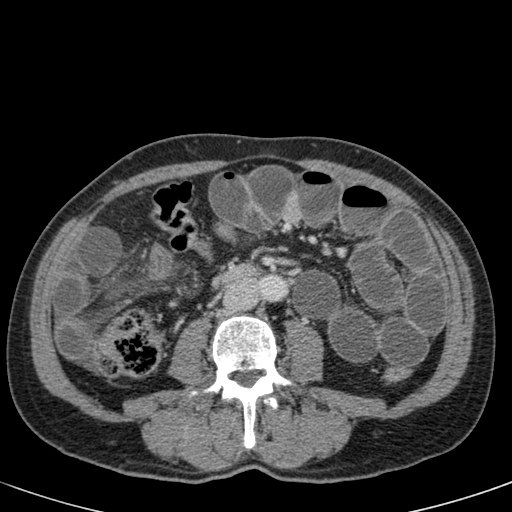

Tắc ruột dạng quai kín với các quai ruột giãn xếp theo hình nan hoa. Có dày thành ruột và phù nề mạc treo gợi ý thiếu máu cục bộ

Một hình ảnh quan trọng khác của tắc ruột dạng quai kín là các quai ruột non giãn xếp theo hình nan hoa với các mạch máu mạc treo hội tụ về một điểm trung tâm.

Hình ảnh này hầu như luôn do xoắn ruột non gây ra.

Các dấu hiệu thiếu máu cục bộ trong tắc ruột dạng quai kín tương tự như ở bệnh nhân thiếu máu mạc treo do các nguyên nhân khác:

- dày thành ruột

- phù nề mạc treo

- cổ trướng

- sự ngấm thuốc của thành ruột trong thiếu máu cục bộ có thể bình thường, tăng hoặc giảm.

Ca lâm sàng bên trái cho thấy một bệnh nhân khác bị tắc ruột dạng quai kín.

Mặc dù các mạch máu ngấm thuốc tốt, nhưng dường như thành ruột không ngấm thuốc.

Các dấu hiệu thiếu máu cục bộ khác trong ca này bao gồm phù nề mạc treo và dày thành ruột.

Ruột bị nhồi máu được phát hiện trong quá trình phẫu thuật.

Nếu quai kín dài hơn và định hướng vuông góc với mặt phẳng cắt, chúng ta sẽ thấy một cụm quai ruột như trong ca lâm sàng bên trái.

Đôi khi điều này khó nhận biết chỉ trên các lát cắt ngang và các tái tạo mặt phẳng coronal hoặc sagittal có thể hữu ích.

Trong ca này, cũng có phù nề mạc treo và cổ